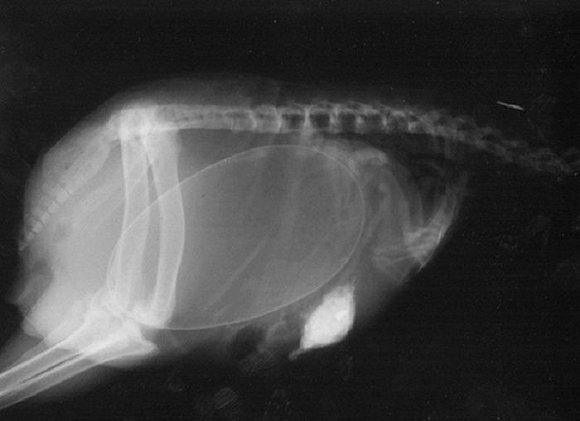

可爱又毛骨悚然 怀孕动物的X光片

人类之间分享母亲肚子里胎儿的X光片是一件非常常见的事情,但是,纵使你觉得自己对X光片已经见怪不怪,在看到了下面这些怀孕动物的X光片后你仍旧会说"哦我的天哪"。

以下就是一些动物在怀孕时的X光片。

1. 乌龟